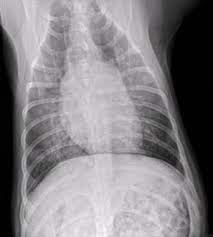

Pneumonia Dog Lung Cancer Xray : The Benefit Of Three View And Left Lateral Thoracic And Abdominal Radiographs Tips For Taking Radiographs In Your Veterinary Practice 2 Important Tips For Taking X Rays In Your Veterinary Practice Tips For Taking X Rays / Pneumonia in dogs can have different causes:. Lung cancer often misdiagnosed as pneumonia urges requests for second medical opinions. Signs of the primary tumors in dogs. Typical signs of bacterial pneumonia include fever, difficulty breathing, lethargy and coughing. The first of these possibilities could be investigated by bronchoscopy. The second kind of lung cancer in dogs is called metastatic lung cancer, which means the cancer originated somewhere else in the body, but has spread to the lung.

Aspiration Pneumonia In Dogs Central Toronto Veterinary Referral Clinic from ctvrc.ca A definitive diagnosis of lung cancer requires a sample of tissue (biopsy). Pneumonia is a lung infection that leads to breathing difficulties and fluid in the lungs. But in some rare cases, it may be a lung cancer (primary or secondary). My dog had pneumonia come on quickly this last august, we took her to the local er at 3am when we noticed her breathing labored and strange behavior. X rays are very helpful in the diagnosis of lung cancer in dogs. Typical signs of bacterial pneumonia include fever, difficulty breathing, lethargy and coughing. A retrospective study of 1011 hospitalized patients with pneumonia was undertaken to assess the value of routine convalescent chest radiography for detection of underlying lung cancer. The bronchioles end in the small sacs called.

A definitive diagnosis of lung cancer requires a sample of tissue (biopsy). X rays are very helpful in the diagnosis of lung cancer in dogs. Primary lung cancer are frequently located in the caudal (towards the hind end of the pet) lung lobes, however can be located in any lung lobe and are usually a single mass in the lungs, unless the tumor has spread. If your dog has a chronic cough, you'll need to rule these out. The first of these possibilities could be investigated by bronchoscopy. A definitive diagnosis of lung cancer requires a sample of tissue (biopsy). The second kind of lung cancer in dogs is called metastatic lung cancer, which means the cancer originated somewhere else in the body, but has spread to the lung. Bacterial pneumonia is an inflammation of the lung usually caused by bacterial or viral infection but can be caused by inhalation of an irritant. The respiratory system consists of the large and small airways and the lungs. Lung cancer is actually the number one killer when it comes to cancers. But in some rare cases, it may be a lung cancer (primary or secondary). In both cases, you may have. Typical signs of bacterial pneumonia include fever, difficulty breathing, lethargy and coughing.

Various viruses, bacteria, and fungi can cause pneumonia. Malignant tumors trigger inflammation in surrounding normal lung tissue, and they may obstruct. In both cases, you may have. However, some dogs only experience weight loss (despite a good appetite) and/or lack of energy. This is not to say the effects on a loved dog's body are the same as an infection.